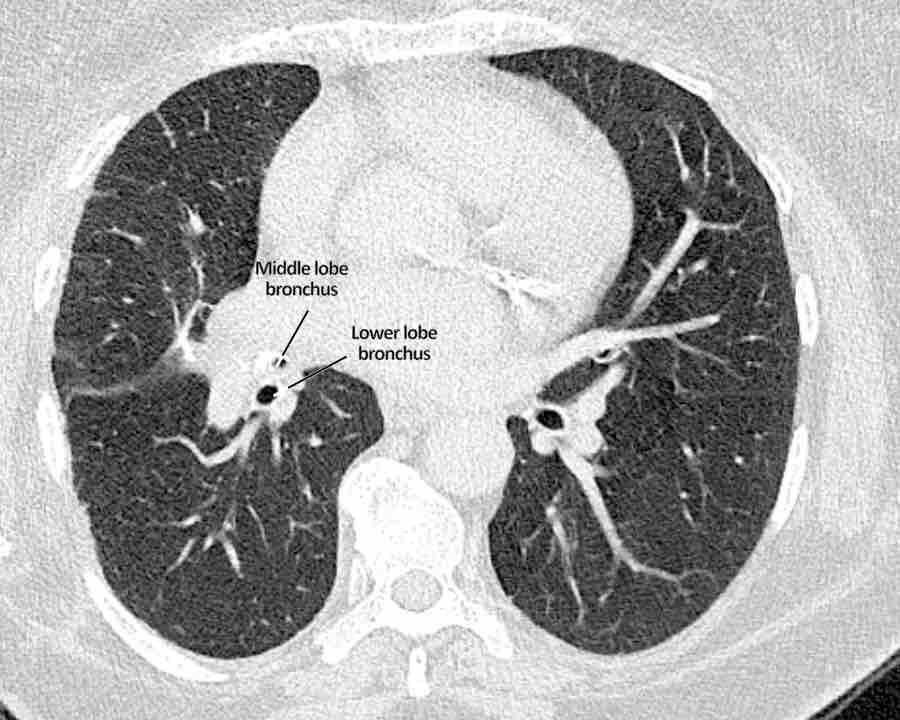

Phế quản trên CT

Cuộn qua các hình ảnh để quan sát khí quản phân chia thành phế quản chính phải và trái, sau đó tiếp tục phân chia thành các phế quản thùy và phế quản phân thùy.

Phế quản thùy trên, phế quản trung gian và phế quản thùy dưới tiếp tục đi về phía ngoại vi.

Phế quản thùy giữa kết thúc tại vị trí đặt các ghim phẫu thuật.